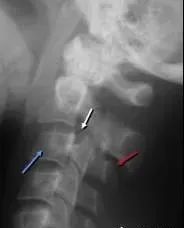

六、泪滴样骨折

屈曲压缩型骨折,可见泪滴样骨碎片向椎体前方分离移位,椎体变扁并向后方移位,椎小关节间隙及棘突间隙增宽,椎间隙变窄,70%合并神经损伤。

七、单纯型压缩性骨折

椎体变扁呈楔形,前缘塌陷>3mm,常累及椎体上终板。